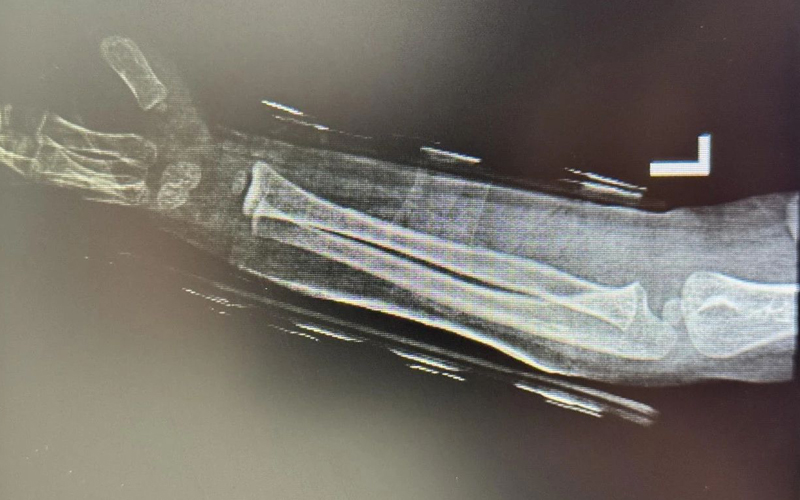

患儿刘某之女今年4岁,因在幼儿园不慎摔伤导致左前臂肿痛难忍急来院就诊,门诊医师行检查显示左前臂尺桡骨双骨折并有骨弯曲,穆中杰教授与科室正骨医师团队立即准备好手法复位所需的杉树皮夹板固定材料,助手固定牵拉患儿左前臂,穆教授在患儿变形的手臂上一压、一按、一推、一挤,再用手在骨折处一捋,随后对紧张的小朋友说:“接好了,你看一点都不疼吧”。随后正骨团队立即使用杉树皮夹板固定好患肢。

为患儿复位中

复位后复查显示骨折基本达解剖复位,迅速恢复使患儿家属欣喜万分,对这位来自杭州的专家十分感激。